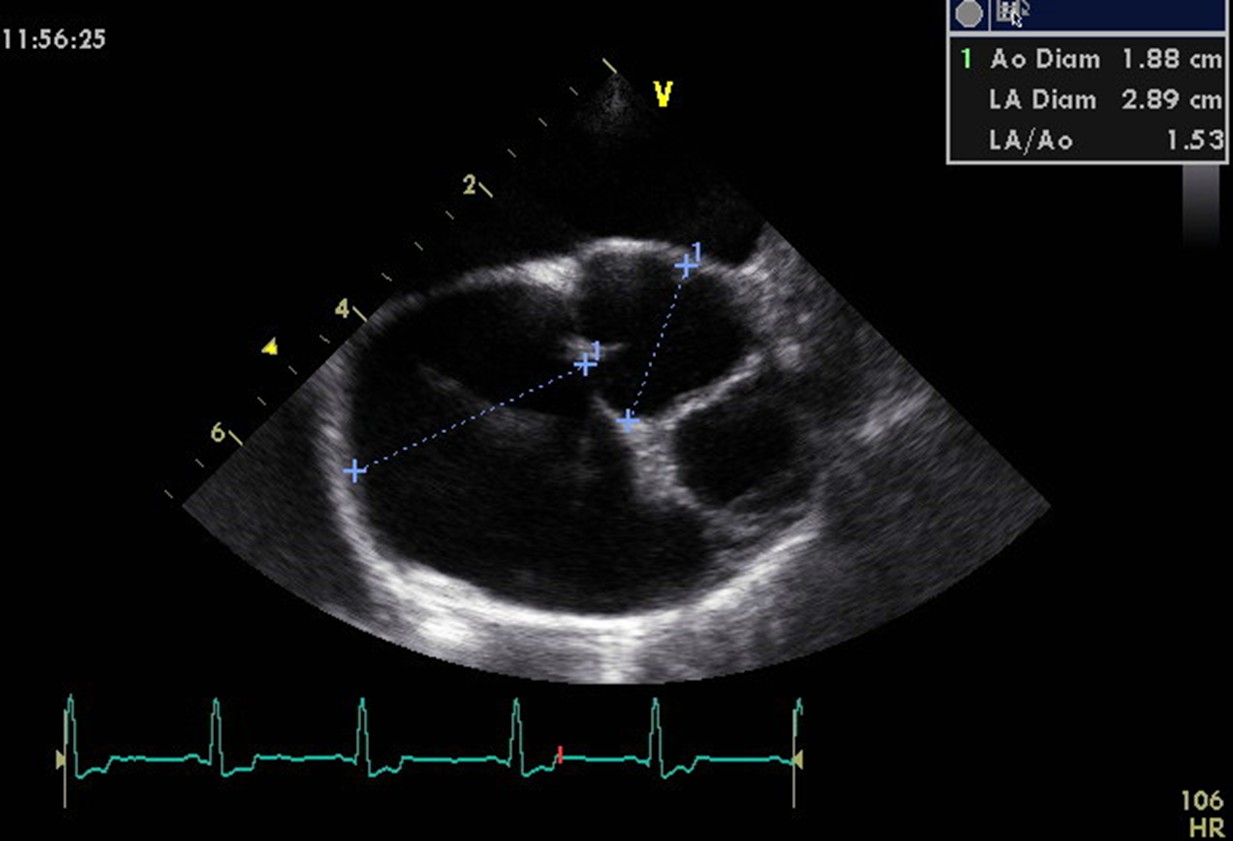

Echo image of the right parasternal short axis view at the level of the aortic valve – used to create the LA/Ao measurement.